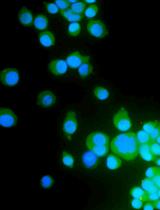

Identification of SARS-CoV-2 Neutralizing Antibody with Pseudotyped Virus-based Test on HEK-293T hACE2 Cells

Neutralizing antibodies (NAbs) are of particular importance because they can prevent binding of the receptor binding domain (RBD) of the spike protein (S protein) to the angiotensin-converting enzyme 2 (ACE2) receptor present at the surface of human cells, preventing virus entry into the host cells. The gold standard method for detection of NAbs is the plaque reduction neutralization test (PRNT). Based on the measurement of cell lysis due to viral infection, this test is able to detect antibodies that prevent cell infection (Muruato et al., 2020; Lau et al., 2021). This technique requires the use of live pathogens, i.e., SARS-CoV-2 in this case, and must be done in a biosafety level 3 (BL3) laboratory. In addition, it requires expensive installations, skillful and meticulous staff, and a high workload, which prevents its wide implementation even in research laboratories. A SARS-CoV-2 pseudovirus will express the S protein responsible for cell entrance, but will not express the pathogenic genetic material of the virus, making them less dangerous for laboratory staff and the environment. Graphic abstract: